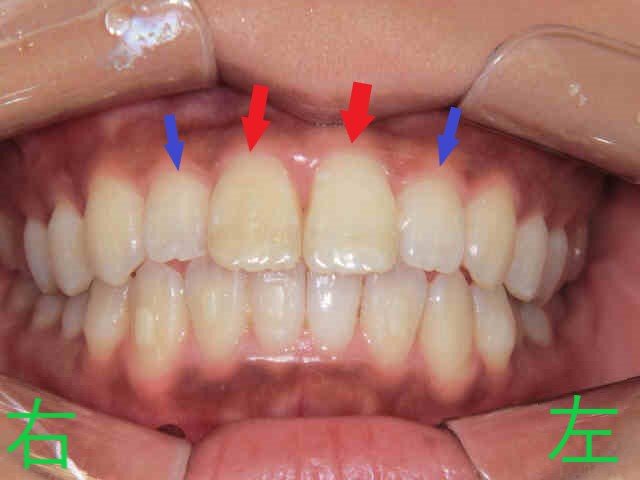

左の写真は、矯正治療開始から3か月後の上顎の様子です。上顎左右中切歯の前突感が緩和され、左右側切歯が内側から外側へと移動しつつあることが確認できます。

右の写真は上下の噛み合わせを下から見上げたもので、下顎前歯が内側に移動し、それに伴い上顎中切歯も内側に移動。前突感の軽減が明瞭です。側切歯の外側移動も進行中ですが、改善の余地が残ります。